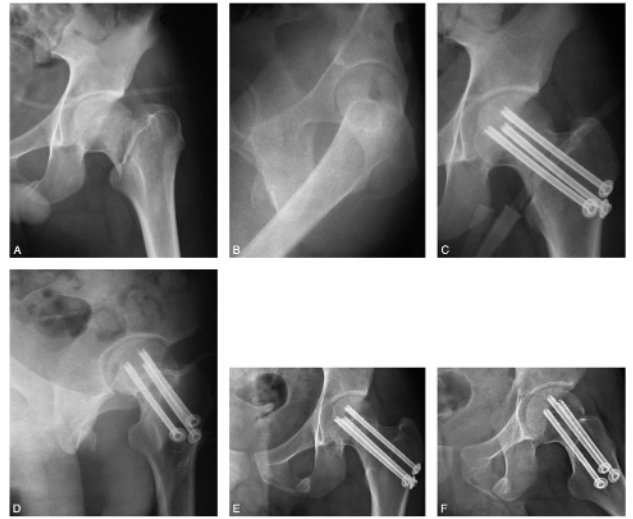

病例简介:患者,男,19岁。因车祸致伤左髋部,伤后4小时来北京积水潭医院急诊,经体检拍片(图62-1),诊断为股骨颈骨折(左,GardenⅣ型)。

图62-1 股骨颈骨折患者术前及术后系列X线片A、B.术前正侧位X线片;C、D.术后当日正侧位X线片;E、F.术后10周正侧位X线片,显示骨折已愈合

股骨颈骨折内固定手术应作为一个相对急诊手术看待,尤其是对于年轻患者更应如此。在伤后12小时内手术有助于减少股骨头缺血坏死的发生。本例患者于伤后11小时行骨折闭合复位,经皮空心钉内固定术。骨折复位及固定良好。

术后复查时可发现“钉尾外退”现象,轻度退钉是愈合过程骨折端吸收所致,不影响骨折愈合。对于退钉较多者,应嘱患者停止负重。骨折愈合后,应每3~6个月复查一次,直至术后3年,以便早期发现股骨头缺血坏死。术后第一天下地,扶双拐部分负重至术后2个月改用单拐,术后3个月弃拐完全负重行走。骨折于术后10周愈合,至术后5年未发生股骨头缺血坏死(图62-1)。